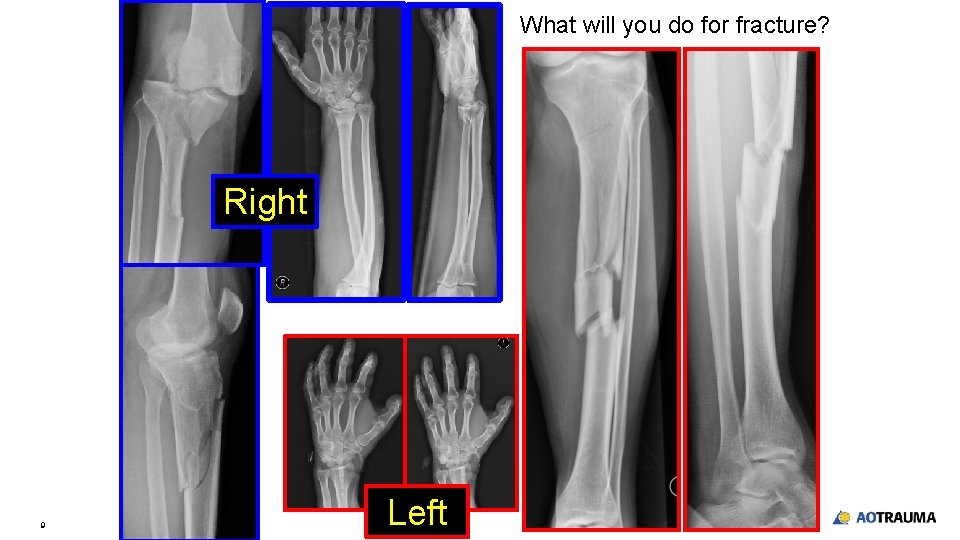

What will you do for fracture? Right 9 Left